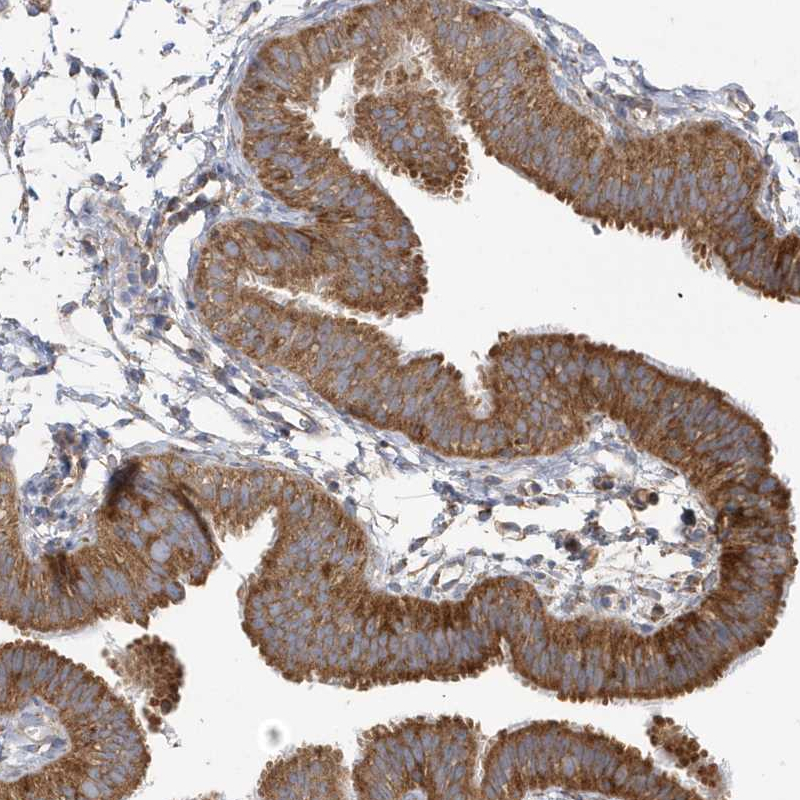

Immunohistochemical staining of human testis shows strong cytoplasmic positivity in cells in seminiferous ducts.